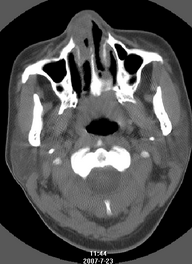

以下是引用还珠格格在2007-7-31 19:32:00的发言:[br]右侧鼻前庭内可见软组织块影,部分鼻中隔包绕其内,邻近骨质未见明显吸收破坏,考虑 1、鼻息肉可能性大 内翻乳头状廇不除外。期待结果。

以下是引用zjzjr在2007-7-31 20:29:00的发言:[br]右侧鼻前庭内可见软组织块影,部分鼻中隔包绕其内,邻近骨质未见明显吸收破坏,考虑 1、鼻息肉可能性大 内翻乳头状廇及肉芽肿类病变除外。期待结果。